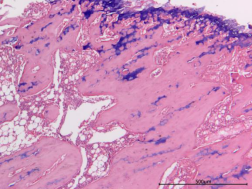

圖1 HE染色圖 40X

樣本中細(xì)胞核被蘇木精染成藍(lán)色;細(xì)胞質(zhì)被伊紅染成深淺不同的粉紅色至深紅色。

蘇木精-伊紅染色法簡稱HE染色法,是最常用的染色方法。蘇木精(hematoxylin)是陽離子染料,能夠?qū)⒓?xì)胞核內(nèi)的嗜堿性物質(zhì)染成藍(lán)紫色。伊紅(eosin)是陰離子染料,能夠?qū)⒓?xì)胞質(zhì)和膠原纖維等染成粉紅色。